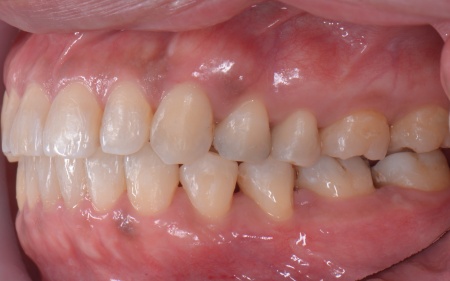

続いて噛み合わせを拝見したところ、前歯がしっかりと噛み合わない開咬(かいこう)という状態です。

この開咬により、本来前歯で分散して受け止めるべき噛む力が、すべて奥歯に集中していることがわかりました。そのため下顎隆起が発生し、また重度歯周病の大きな原因になっていると考えられます。

とくに上の左右奥歯には、矯正用ミニインプラント(矯正治療専用の小さなネジ)を埋入し、奥歯を歯茎の方向に押し下げる「圧下」という治療を行っています。これにより開咬が解消され、前歯でしっかり噛めるようになりました。

最後に、右下奥歯に装着されていた銀の詰め物を外し、強度と審美性に優れた白い被せ物であるジルコニアセラミッククラウンを装着します。見た目や噛み合わせ、使用感などに問題がないことを確認し、治療を終了しました。